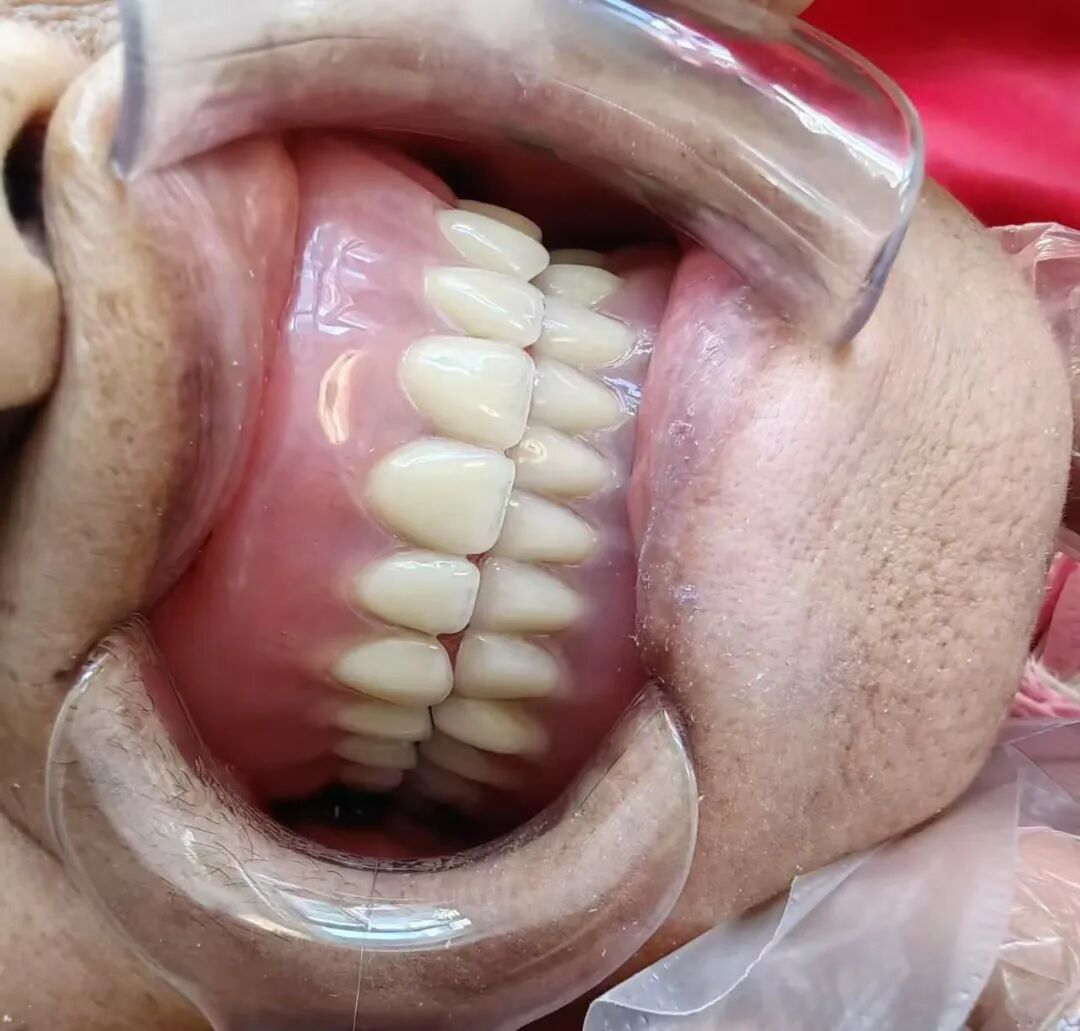

精雕修复 美功兼具

——口腔修复技术提质升级

借助上海闵行区援滇专家高琳教授的对口帮扶,科室口腔修复技术在2026年实现质的飞跃。在高琳教授亲传带教下,科室的贴面、嵌体等微创修复技术及BPS技术均得到系统化提升,诊疗过程中更注重“功能修复+美学设计”双重需求,为每一位患者量身打造独一无二的个性化修复方案,让修复后的牙齿既恢复正常咀嚼功能,又能贴合面部特征实现自然美观,全方位满足患者的口腔修复需求。

治疗前

治疗后